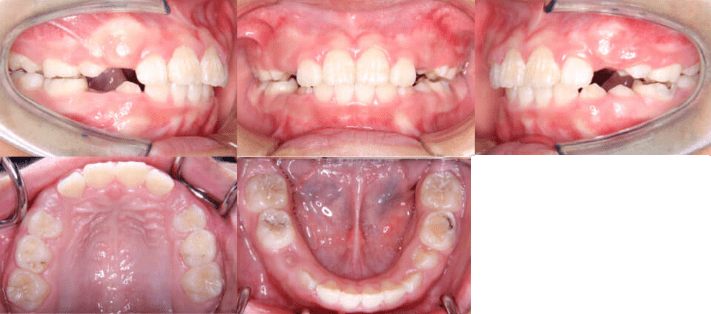

• 初診時年齢:8歳5ヶ月

• 主訴:上の前歯がでていて口が閉じづらい

• 診断:過大なオーバージェットを伴う過蓋咬合症例

• 治療内容:インビザライン・ファースト使用して主訴である上の前歯の突出を改善しつつ、前歯のかみ合わせが深い過蓋咬合についても下の前歯を押し下げて上あごの歯ぐきを噛まなくなるように改善しました。

• 治療期間:10ヶ月

• リスク:矯正治療による歯の移動に伴う痛み、歯根吸収、虫歯

• 費用:40万円